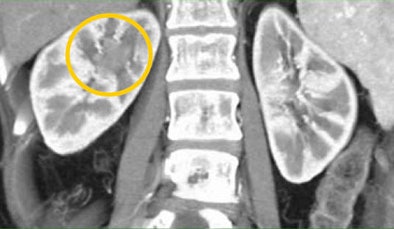

In one patient example, a small hypervascular lesion in the left kidney could not be seen in the early corticomedullary phase, even when the image was viewed in multiple planes, in volume rendering (VR) and maximum-intensity projections (MIPs). It became "a fairly obvious lesion on excretory-phase imaging," Fishman said.

| Subtle renal cell carcinoma not visualized in any plane in the arterial phase (above) becomes fairly obvious in excretory-phase image (below). All images courtesy of Dr. Elliot Fishman. |

CT images from a patient with transitional cell carcinoma (TCC) were also best appreciated in late-phase imaging. The early-phase data showed slight differential diffusion between the right and left kidneys and a subtle lower-density region in the right kidney. With excretory-phase imaging, the TCC was visible in the axial view and was even more clearly defined in the coronal view.

| In a patient with TCC, slight perfusion differences can be seen between the right and left kidneys in the arterial phase (above), and a subtle lower-density zone can be appreciated in the right kidney. On excretory-phase imaging, in both the axial view (below) and coronal view (bottom) it becomes an obvious infiltrative tumor. |